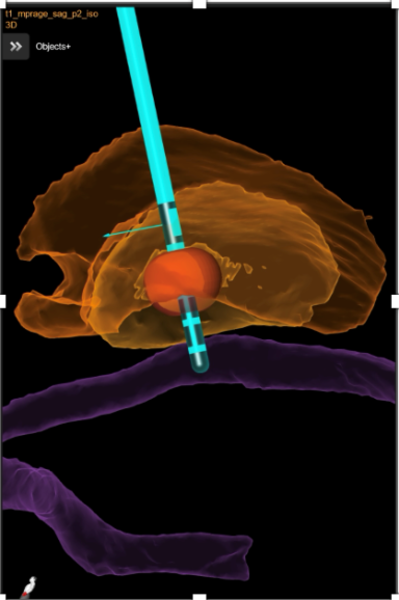

Bei bestimmten Bewegungsstörungen, die nicht oder nicht mehr ausreichend auf eine medikamentöse Therapie ansprechen, ist es möglich, die hierfür verantwortlichen Hirnareale durch die sog. Tiefe Hirnstimulation zu beeinflussen. Hierbei werden feine Elektroden in das Gehirn eingesetzt, um fehlerhafte Nervenstrukturen mit elektrischen Impulsen zu aktivieren oder zu hemmen. Beim Morbus Parkinson, dem essentiellen Tremor oder der Dystonie sind beispielsweise spezifische Hirnareale überaktiv, die dann gezielt durch die Tiefe Hirnstimulation gehemmt und die Symptome wie Zittern oder Muskelsteifigkeit dadurch unterdrückt werden können. Die Hirnregionen selbst bleiben dabei intakt, sodass die Stimulation jederzeit rückgängig gemacht werden kann. Die elektrische Stimulation wird durch einen Impulsgeber gesteuert, der ähnlich wie ein Herzschrittmacher unter die Haut an der Brust der Patient:innen implantiert wird. Die Einstellungen des Impulsgebers lassen sich von außen jederzeit verstellen, sodass die Stimulation an veränderte Bedürfnisse der Patient:innen stets angepasst werden kann.

Neben den Bewegungsstörungen sind mittlerweile auch einige neuropsychiatrische Erkrankungen, wie die Depression oder Zwangsstörungen bekannt, bei denen fehlerhafte Hirnareale durch die Tiefe Hirnstimulation verändert (=moduliert) werden können. Bei schweren therapieresistenten Verläufen kann auch hier dieses Verfahren angeboten werden.